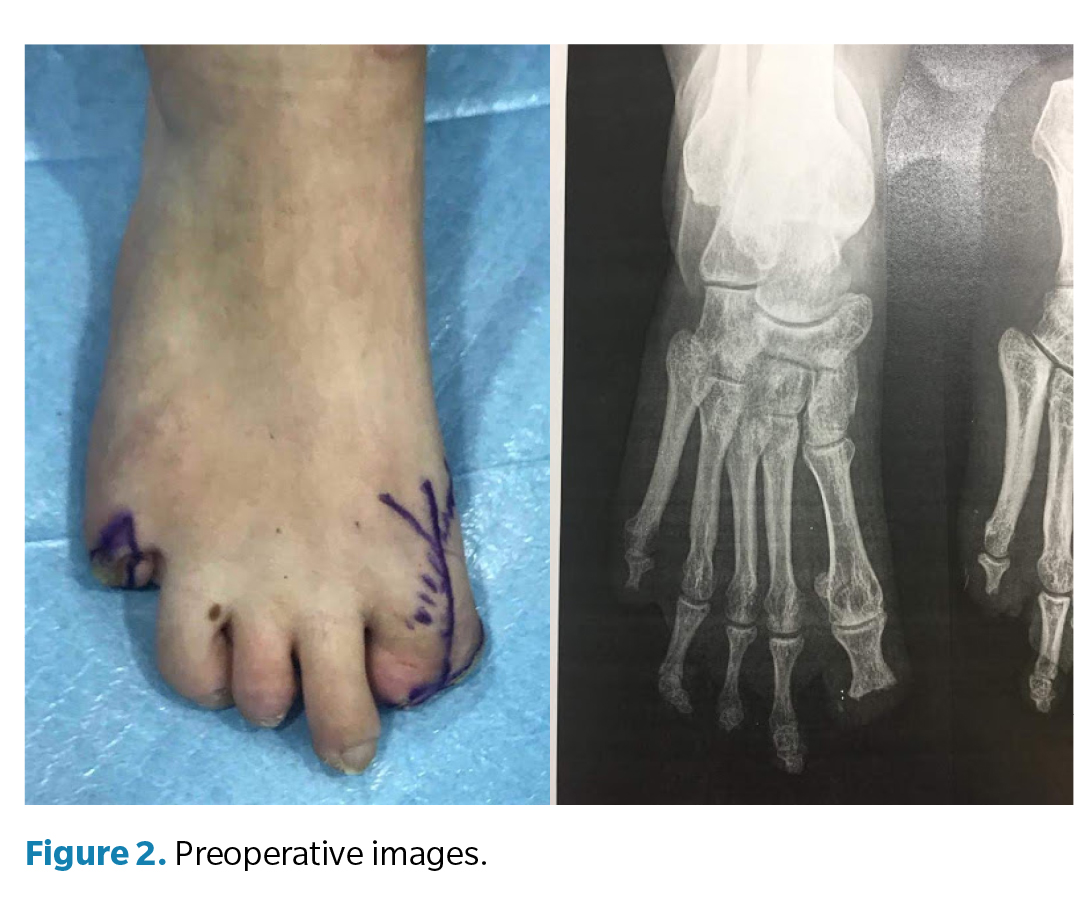

Surgery (Figure 3) was performed in March 2022 under regional anesthesia using a posterior popliteal block and conscdious sedation supervised by an anesthesiologist. Antibiotic prophylaxis with 2 g of IV cefazolin was administered 30 minutes before incision, and a pneumatic ankle tourniquet was applied (250 mm Hg), with controlled pressure and ischemia time limited to 45 minutes. A longitudinal dorsal approach to the first metatarsophalangeal joint was performed, preserving neurovascular structures. Irregular bony remnants of the proximal phalanx were identified and completely resected, followed by contouring of bone margins to achieve smooth, viable surfaces. Articular surfaces of the first metatarsophalangeal joint were then prepared by burring and curettage until an adequate bleeding base for arthrodesis was obtained. Fusion position was determined intraoperatively under load testing, fixing the hallux at approximately 10° dorsiflexion relative to weightbearing surface to optimize propulsion and prevent plantar overload on the residual stump. Final fixation was achieved using one cannulated compression screw, ensuring intraoperative stability and correct alignment under fluoroscopy (Figure 4). The procedure concluded uneventfully, with meticulous hemostasis and layered closure.

The postoperative period included periodic dry dressings and progressive functional follow-up. At 3 months, complete pain resolution and significant improvement in gait quality were observed. At 6 months, the patient showed satisfactory functional recovery, allowing temporary medical discharge. Customized silicone digital prostheses were later fabricated for both feet to improve podiatric symmetry, load distribution, and psychosocial acceptance. At 12-month follow-up, the patient remained asymptomatic, with complete radiographic consolidation of the arthrodesis, correct alignment of the first ray, and stable gait without limitations, confirming the functional success of the procedure.